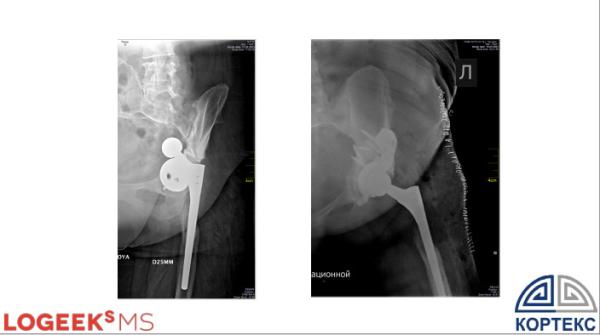

По словам докладчика, первая операция с применением индивидуальных имплантатов — эндопротезирование тазобедренного сустава — проведена в хирургическом центре «Кортекс» в ноябре 2022 года.

На май 2025 года проведено 18 операций первичного и ревизионного эндопротезирования тазобедренного сустава с замещением дефектов костной ткани индивидуальными имплантатами.